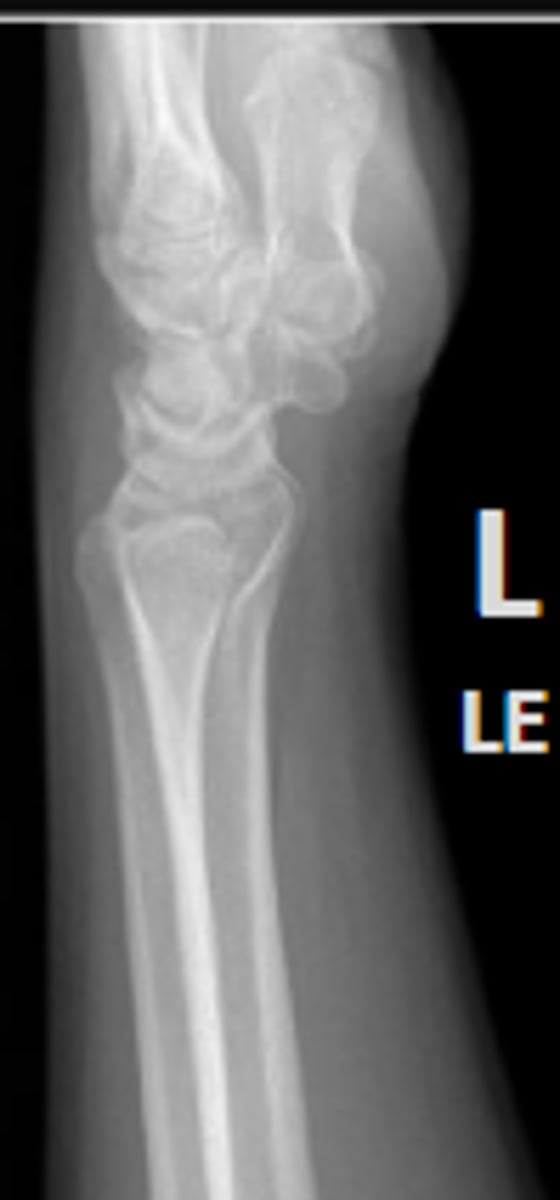

Left lateral wrist

What is the name of the radiographic view?